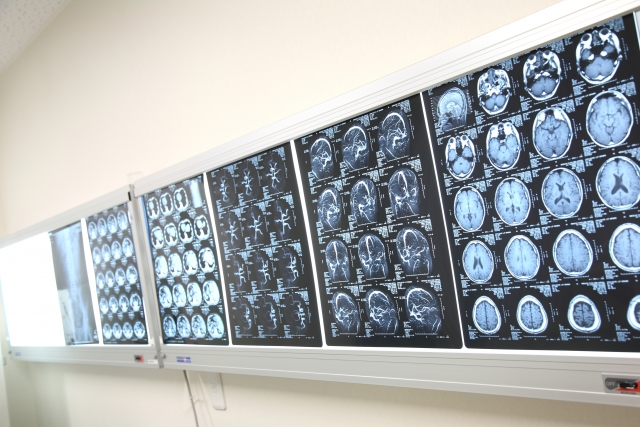

健診センターでは、富士フイルムが持つCTスキャン・マンモグラフィなどの医療機器や医師の診断を支援するAI技術を活用して、すべての検査と医師による健診結果のフィードバックが、約120分という短時間で完了する点や、フィードバックの際に、医師から健診結果に関する説明を診断画像を見ながら分かりやすく受けられる点などが好評を得ているという。